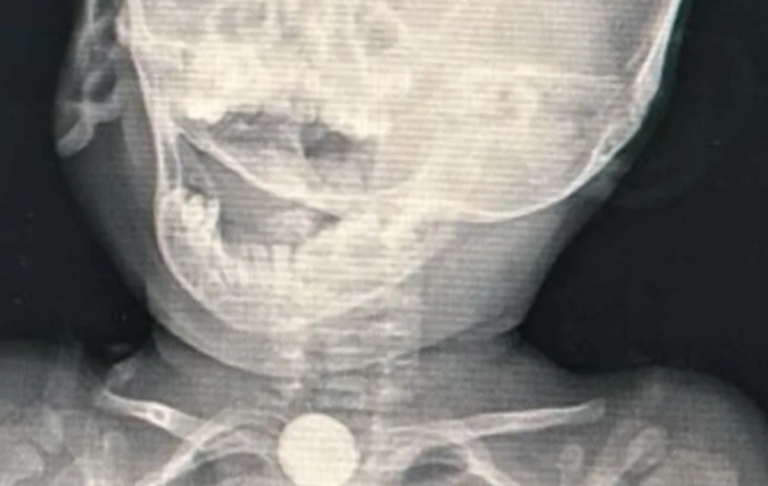

A bateria deveria ter sido removida em no máximo duas horas, mas passou dois dias no corpo do bebê/Foto: Reprodução

A bateria deveria ter sido removida em até duas horas após a ingestão, já que ela pode se romper e soltar diversos elementos químicos no interior do corpo, podendo causar lesões na mucosa do esôfago.